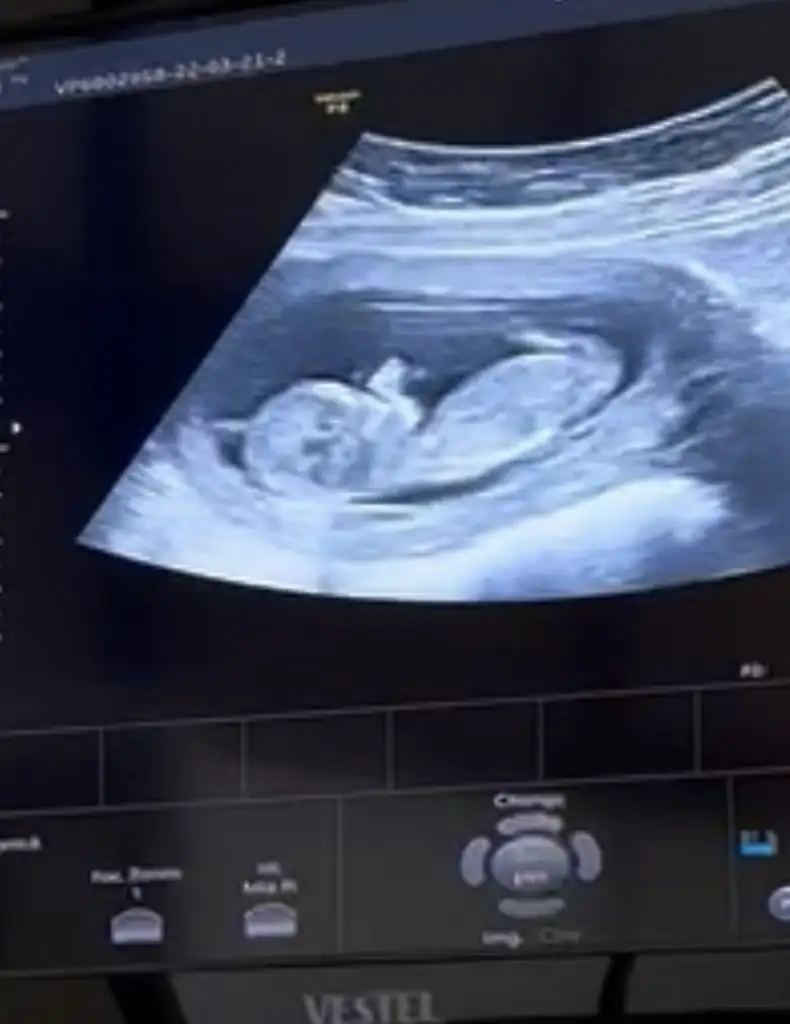

Kız olabilir belki erkek kendini erken belli ediyor sanırım 11+3te görmüştük bizKızlar bizde 12+2 olduk. Doktor cinsiyet için çok erken dedi 3 hafta sonra tekrardan çağırdı. Cinsiyet tahmini yapanlar kimlerdi etiketleyemedim beceremedim :) Eki Görüntüle 3030734

Birazda doktorun ultrasonu ile.alakali benceKız olabilir belki erkek kendini erken belli ediyor sanırım 11+3te görmüştük biz![]()